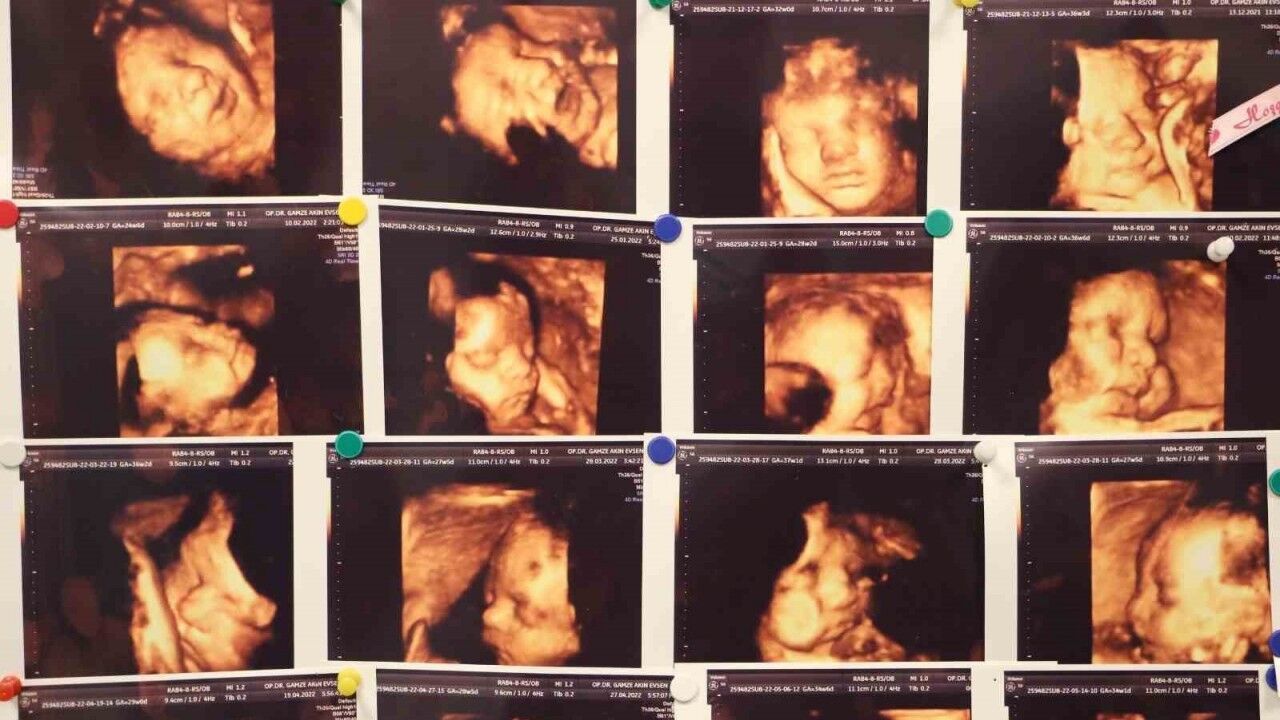

Memorial Hastanesi Kadın Hastalıkları ve Doğum Uzmanı Op. Dr. Gamze Akın Evsen, çocuk sahibi olmaya hazırlanan çiftlerin yaşadığı en büyük travmalardan biri olan gebelik kayıpları, çoğu anne adayının psikolojisinin bozulmasına ve çaresizlik hissine kapılmasına neden olduğunu belirterek, "Klinik olarak saptanan gebeliklerin yüzde 10-15’i düşükle sonuçlanmakla beraber bu durumun tekrar etmesi yani tekrarlayan gebelik kayıplarında oran Yüzde 3 ila 5’tir" dedi.

Anne olma kuramının başlangıcı olan karar ve hazırlık aşamasında kötü deneyimi olmayan kadınlarda daha rahat geçtiğini söyleyen Dr. Evsen, "Olumsuz deneyim yaşamış kadınlarda ise zorlayıcı geçmektedir. Anne, gebe kalınıp her şey yolunda olsa bile beklenen bir bebeğin heyecanını kaybetme endişesi ile beraber yaşamaktadır. Zorlu süreçlerden sonra elde edilen gebeliklerde gebelik süresince anne adayları süreçle ilgili zorluklarda bile şikayet etme haklarının olmadığını düşünüp sadece minnettarlık duyması gerektiğini düşünebilirler. Gebelik oluştuğu andan itibaren kaybetme korkusu hakim olduğundan anne adayı gebeliğe inanmakta güçlük çekebilir sık kontroller sık testler yaptırabilir” ifadelerinde bulundu.